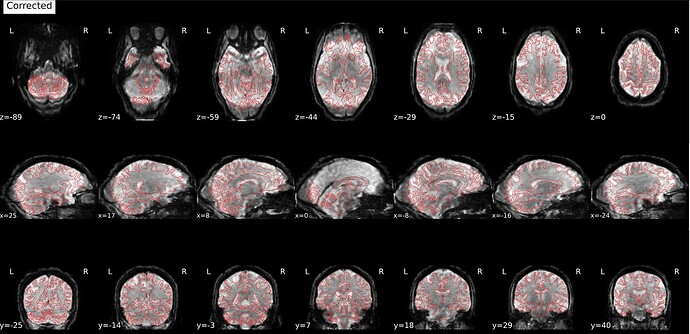

Hi everyone! I’m currently trying to use fMRIPrep to preprocess a dataset from openneuro (ds006072). fMRIPrep is running smoothly in general, but there seems to be a problem with SDC, which leads to a distorted and elongated corrected image. This is one example, but the data for all my sessions is similarly distorted:

This is what the distorted version looks like, before SDC: